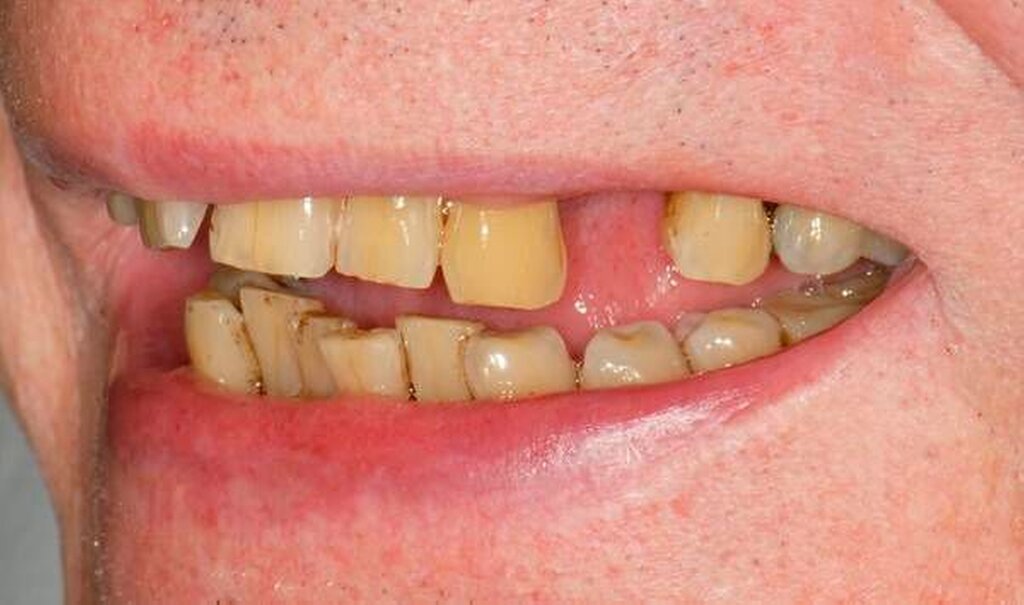

Abbildung 4: Überwachtes Monitoring (Belassen und Beobachten) von Zahnlücken

In der Zahnmedizin ist ein Dogma weit verbreitet: „Jede Lücke muss rasch geschlossen werden.“ Tatsächlich gibt es jedoch viele Situationen, in denen es ohne relevante funktionelle und ästhetische Einbußen vertretbar erscheint, eine Lücke zu belassen und regelmäßig zu beobachten (Monitoring). Derzeit erfolgt die Entscheidung „Lücke belassen versus Lücke schließen“ oftmals subjektiv. Sie ist zuweilen weniger von den Patientenvariablen abhängig als von den Schwerpunkten der betreuenden Zahnärzte (Abbildung 4) [Listl et al., 2016]. Ein fachlich fundiertes Vorgehen, das eine Entscheidung unter einer Nutzen-Risiko-Abwägung trifft und ein Monitoring in die Überlegungen einbezieht, kann ebenfalls in die Kategorie der frugalen Interventionen eingeordnet werden. Gleiches gilt für ein Vorgehen im Sinne des Prinzips der verkürzten Zahnreihe, das inzwischen wissenschaftlich gut evaluiert ist [Walter, 2016] und zu dessen Realisierung auch konservierende Maßnahmen beitragen können (Abbildung 5).

Falls ein Lückenschluss nach Gegenüberstellung der Vor- und Nachteile als angemessen angesehen wird, stellt sich die Frage, mit welchen Hilfsmitteln dies erfolgen soll. Derzeit stehen Implantate und klassische Brückenversorgungen im Vordergrund. Es gibt aber auch etliche nicht- oder minimal-invasive Alternativen, die zum Beispiel bei Einzelzahnlücken in Erwägung gezogen werden können. Dazu zählen unter anderem direkte Verfahren wie Zahnverbreiterungen oder -anhänger (Abbildungen 6 und 7) [Staehle, 2009 und 2012; Staehle et al., 2015]. Zurzeit kommen derartige Maßnahmen nur in Einzelfällen in Betracht, es bedarf noch weiterer Evaluationen, um ihr Indikationsspektrum genauer abgrenzen zu können. Es zeichnet sich aber jetzt schon ab, dass sie ein gewisses Potenzial als frugale Interventionen besitzen. Auch wenn momentan vielfach Implantate favorisiert werden, erscheint es dennoch sinnvoll, wenn die Zahnärzteschaft auch diverse Implantat-Alternativen vorhalten kann. Ungeklärte Probleme periimplantärer Entzündungen [Chrcanovic et al., 2016] und die zu erwartende Diskussion über Beziehungen zwischen periimplantären Entzündungen und der Allgemeingesundheit lassen es als sinnvoll erscheinen, solchen Fragen intensiver als bisher nachzugehen. Bislang wird zwar nur über Einflüsse der Allgemeingesundheit auf den Erfolg beziehungsweise Misserfolg von Implantaten diskutiert. Es ist aber nicht auszuschließen, dass man künftig die Fragestellung in umgekehrter Richtung dahingehend erweitert, inwieweit Implantate ihrerseits nicht nur positiven, sondern auch negativen Einfluss auf die Allgemeingesundheit nehmen können.